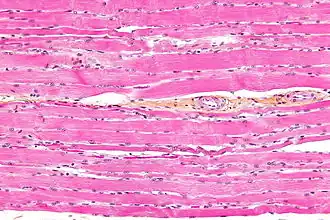

Striated muscle tissue is a muscle tissue that features repeating functional units called sarcomeres. Under the microscope, sarcomeres are visible along muscle fibers, giving a striated appearance to the tissue. The two types of striated muscle are skeletal muscle and cardiac muscle.

Skeletal muscle includes skeletal muscle fibers, blood vessels, nerve fibers, and connective tissue. Skeletal muscle is wrapped in epimysium, allowing structural integrity of the muscle despite contractions. The perimysium organizes the muscle fibers, which are encased in collagen and endomysium, into fascicles. Each muscle fiber contains sarcolemma, sarcoplasm, and sarcoplasmic reticulum. The functional unit of a muscle fiber is called a sarcomere.[2] Each muscle cell contains myofibrils composed of actin and myosin myofilaments repeated as a sarcomere.[3] Many nuclei are present in each muscle cell placed at regular intervals beneath the sarcolemma.